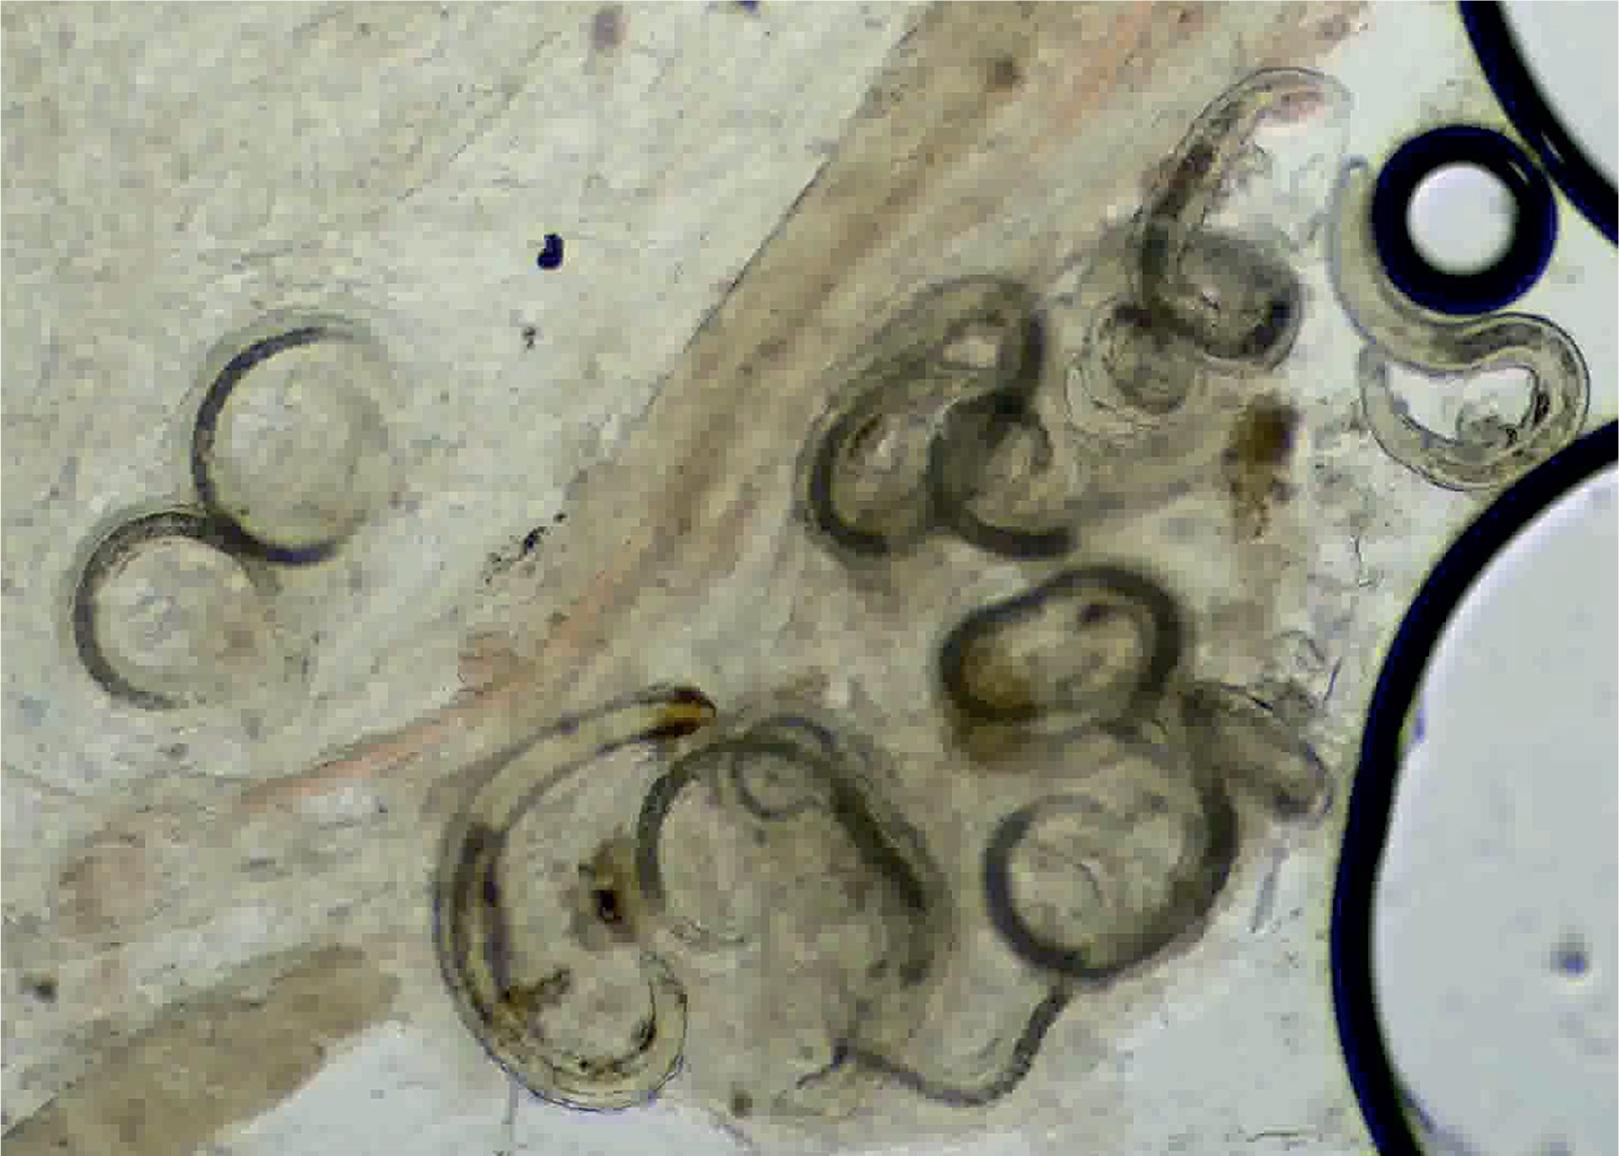

The earthworms were examined for the presence of eggs and larvae of Syngamus trachea: parasitological dissection of the earthworm body with the capture of the contents of the entire digestive tract, similarly to the fecal examination, the contents of the digestive tract were examined by coprological flotation methods and qualitative and quantitative propagation stages of Syngamus trachea were identified during examination of the contents of the digestive tract of earthworms (Clapham, 1997). The body walls of earthworms were examined through a thorough microscopic evaluation of compression slides to confirm the positive findings of encysted L3 larvae in hyaline cysts within the earthworms’ bodies.

A parasitological necropsy of a bird involves a detailed post-mortem examination to identify internal and external parasites. In short, the process begins with external examination for lesions or discharges, followed by incisions to the body cavity to assess internal organs, air sacs, and the gastrointestinal tract for parasites, abnormalities, and changes in tissue consistency, size, or color. Samples of organs and contents are collected for further analysis, including microscopic examination for parasites (Van Riper, 1980). Figures 1 – 2 show the trachea in situ, highlighting the presence of S. trachea within its structure. Figure 3 illustrates infectious larvae L3 encysted in the earthworm’s body wall.

Infectious L3 larvae of Syngamus trachea encysted in the body wall of earthworm – compression microscope slide, magnification 10x.